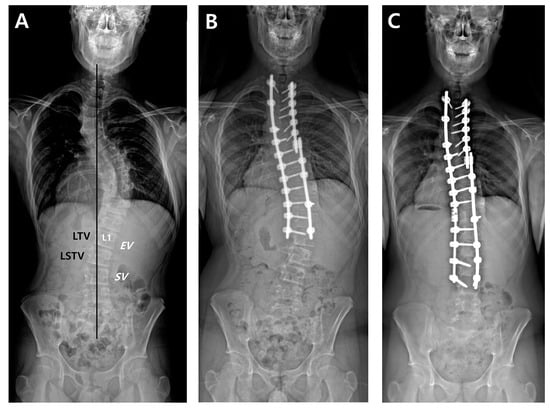

2.4. Radiographic Measurements

For all patients, whole-spine standing posteroanterior, lateral, and fulcrum bending radiographs were taken preoperatively. After surgery, standing posteroanterior and lateral whole-spine radiographs were performed at six weeks, three months, six months, and then annually as part of a routine evaluation of all scoliosis cases. First, we designated radiographic parameters such as EV, NV, and SV on a preoperative whole-spine AP radiograph (Figure 1). The last touching vertebra (LTV) and last substantially touching vertebra (LSTV) were measured using CSVL. On the same radiograph, the nine suggested LIVs according to the selection criteria were separately recorded. Then, we compared the location of suggested LIVs and the actual LIV, and evaluated whether the actual LIV was the same, proximal, or distal relative to the suggested LIV. DA was defined as a progressive increase in the number of vertebrae included within the distal curve, with either an increase of more than 5 mm in the deviation of the first vertebra below the instrumentation from the CSVL or an increase of more than 5° in the angulation of the first disc below the instrumentation [7]. Finally, the preoperative Cobb’s angle (CA) of the main thoracic curve (MTC), flexibility of the MTC, postoperative CA of the MTC, and correction rate of the MTC were measured.

Figure 1.

A thirteen-year-old male underwent posterior fusion from T1 to L1 for AIS of Lenke type 2A curves (A,B). Revision surgery with fusion extension to L3 was carried out due to the development and progression of DA (C). According to the nine LIV selection criteria, the postoperative actual LIV (L1) met the criteria by Wang, Sarlak, Matsumoto, and Fischer. The location of the postoperative LIV was proximal to the suggested LIVs by King (L3), Suk (L3), Parisini (L2), Takahashi (L4), and Qin (L2).